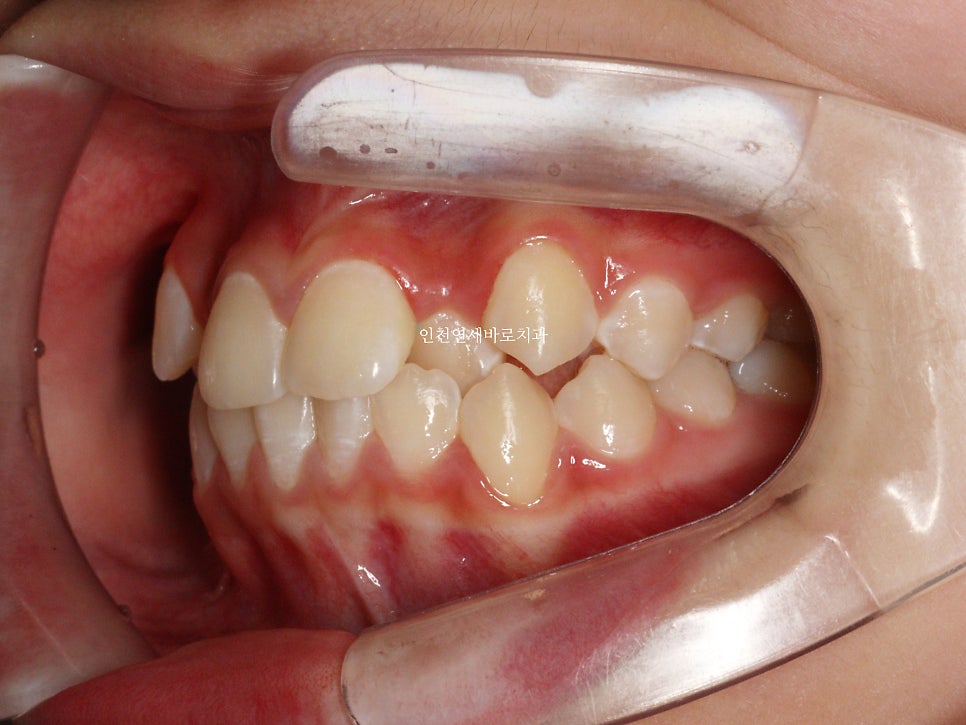

두번째 치아가 덧니로 있는 경우의 치료는 흔한 경우지만

생각보다 많은 노하우가 필요한 치료라고 생각합니다.

교정 치료 중에 화살표 최후방 치아가 맹출하여,

이 치아를 배열하는 과정에서 치료가 조금 더 길어지긴 했습니다

최후방 치아가 나올때 약간 삐뚤게 나옴으로 인해 1회 재제작을 했습니다.